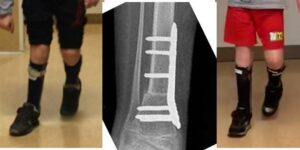

Deformità torsionali degli arti inferiori nel mielomeningocele

Deformità torsionali (rotatorie) degli arti inferiori (in particolar modo la torsione tibiale esterna) sono piuttosto frequenti nei pazienti deambulanti con mielomeningocele e possono provocare disturbi nell’utilizzo dei tutori e nella deambulazione.

Dopo accurata valutazione clinica ed eventuale ricostruzione TC degli assi torsionali, può essere indicato un intervento di osteotomia derotativa.